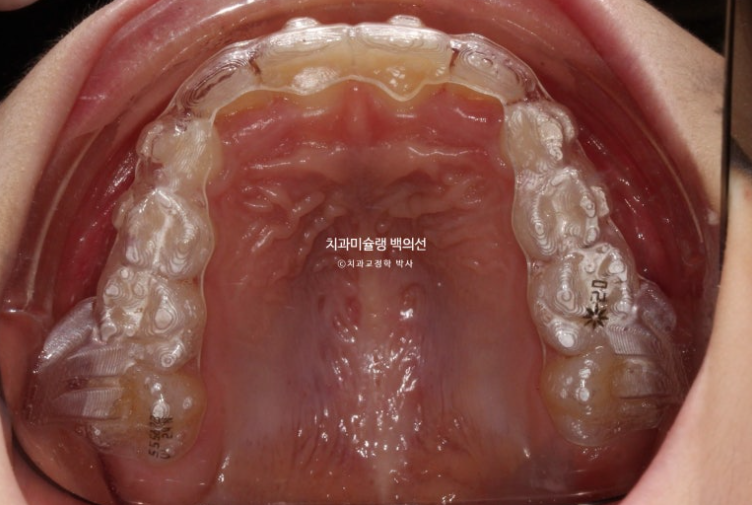

23년 6월부터 11월까지 6개월간 전반부 치료를 끝낸 모습입니다.

23.11

악궁확장을 통해 확보된 공간으로 앞니 덧니가 잘 내려오고 있습니다.

악궁확장을 통해 넓어진 악궁